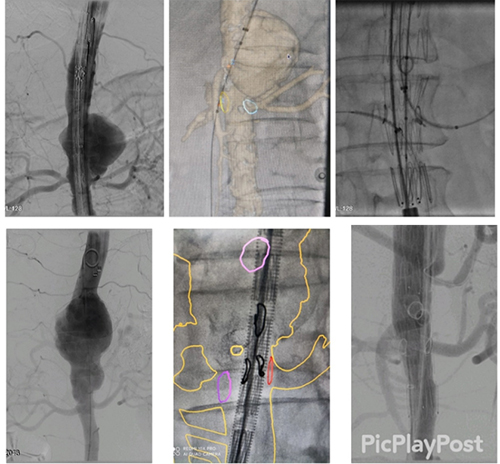

影像融合技术的开展应用便利了手术重建内脏动脉分支,可以减少造影剂用量,缩短手术时间,有效降低围手术期的并发症发生率

改制开窗-分支支架治疗腹主动脉瘤腔内修复术后近端内漏,采用内分支技术重建双肾动脉血流,有效减少窗口内漏几率,分支形态自然,术前内漏消失